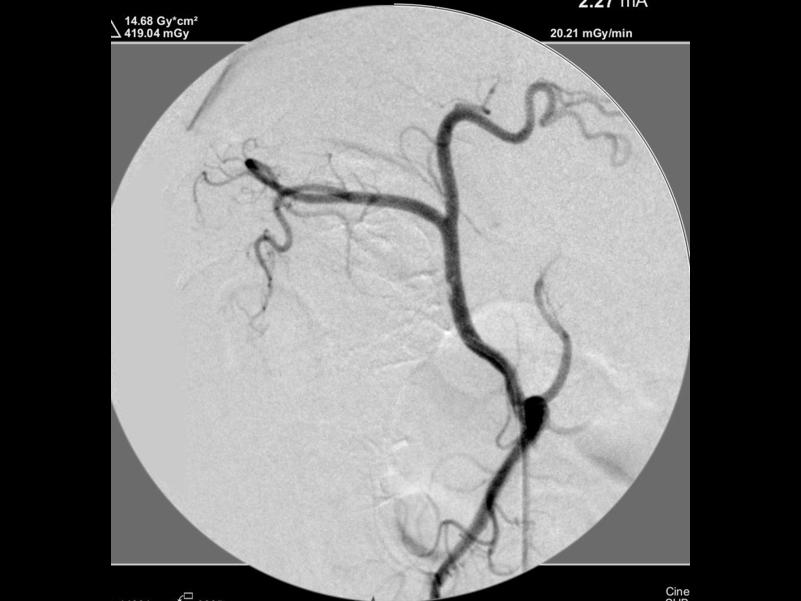

カテーテルでの造影検査